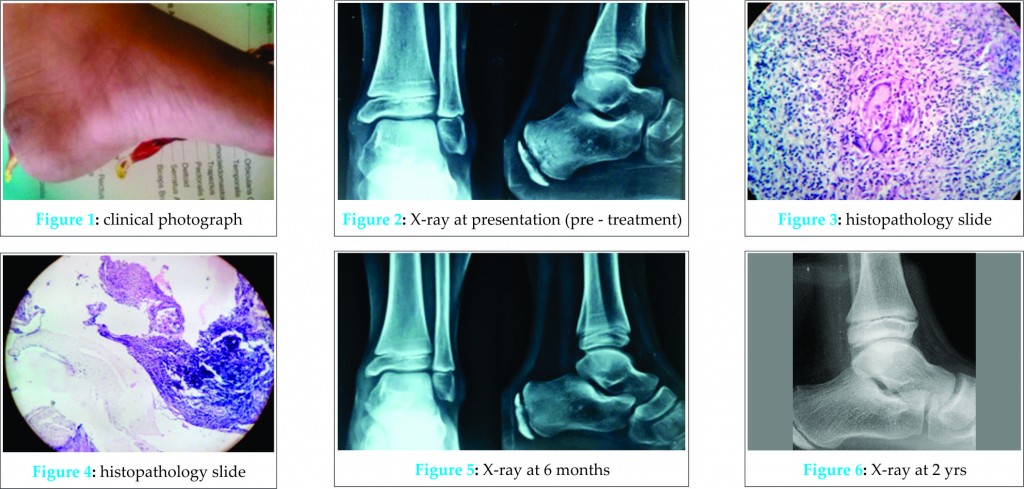

Case presentation: 8 yr old girl presented to OPD with swelling and dull aching pain over left heel. Radiograph of calcaneum showed small lytic puctate lesions in the calcaneum. Further investigations showed presence of multiple tuberculous bacilli. Anti-Kochs treatment was started immediately and patient was treated conservatively. Four drugs (HRZE) were prescribed for a period of 12 months. Radiographs at 2 years follow-up showed a healed lesion.

8 yr old girl presented to OPD with swelling, dull aching pain and unable to bear weight over left heel (tip-toe walking) since four months. Clinically, there was swelling over the ball of calcaneum with tenderness on deep pressure. Local temperature was not raised, with absence of discharging sinus. Inguinal lymphnodes were not palpable. Radiograph of calcaneum lateral view showed small lytic puctate lesions of various sizes in the metaphyseal region of the calcaneum and epiphysis was spared. The patient was further investigated. Investigations showed raised ESR with lymphocytosis. Aspiration biopsy and smear stained with Zeil Nelson stain showed presence of multiple tuberculous bacilli. Anti-Kochs treatment was started immediately and patient was kept under close observation and was treated conservatively. Four drugs (HRZE) were prescribed for a period of 12 months. Radiographs and blood tests were performed every 3 months until treatment completion. Non-weight bearing walking was advised, and foot was protected in a below knee slab for 6 weeks. Partial weight bearing was allowed at 6 weeks and progressed to full weight bearing at 10 weeks. Two years follow-up didn’t show any increase in the size of the lytic lesion. Clinically, pain and swelling subsided and patient’s general condition also improved. Radiographs at 2 years follow-up showed a healed lesion.